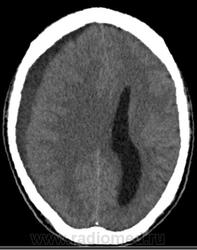

Обнаружено: состояние после фронтотомии;

-над лобной, височной и теменной долями правого полушария большого мозга определяется скопление патологического содержимого плотностью до +20HU, размерами 122х14х98мм(V~87см3)- субдуральная эмпиема, размеры ранее описываемого участка гиподенсной плотности в полюсно-базальных отделах правой лобной доли (+25+30Hu), увеличились до 36х11мм. Смещение срединных структур влево до 10мм.

К делу подключились нейрохирурги, больной был экстренно прооперирован. Произведена КПТЧ, удаление субдуральной эмпиемы лобно-височно-теменной области справа, постановки дренажа под ТМО. Также вскрыты передние стенки обоих гайморовых пазух, произведена ревизия лобной пазухи, в пазухи заведены тампоны. По образному выражению нейрохирурга, при вскрытии ТМО получили: "Фонтан гноя". Снимки после операции: